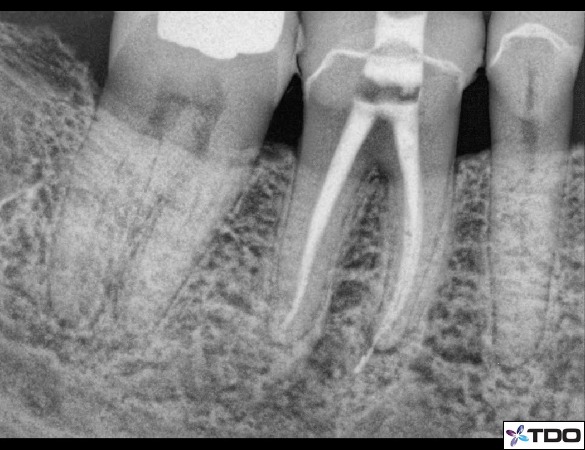

Figure 7: A conservative access form with a convergence towards the occlusal and preservation of mesial tooth structure.

Figure 8: Another access form with convergence towards the occlusal. This access cavity is quite centralized in the molar in both the mesial to distal direction and buccal to lingual direction.